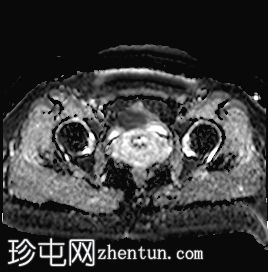

轴位

STIR序列

可见子宫外腹腔内妊娠囊,内含胎儿组织。

沿妊娠囊下缘可见一处异质性局灶性积液,最大轴向尺寸约为 8.4 × 5.5 cm,T1 加权像呈异质性高信号,T2 加权像呈异质性中等信号,T1 脂肪抑制序列未见信号下降,提示为血液成分。该积液压迫膀胱。

右侧卵巢未见实性或囊性肿块。

子宫体积增大,后倾,子宫内膜厚度约 1 cm,子宫下段前壁可见局灶性变薄(既往子宫瘢痕)。子宫连接区完整,未见肌层肿块。可见子宫内膜腔边缘有血性分泌物。